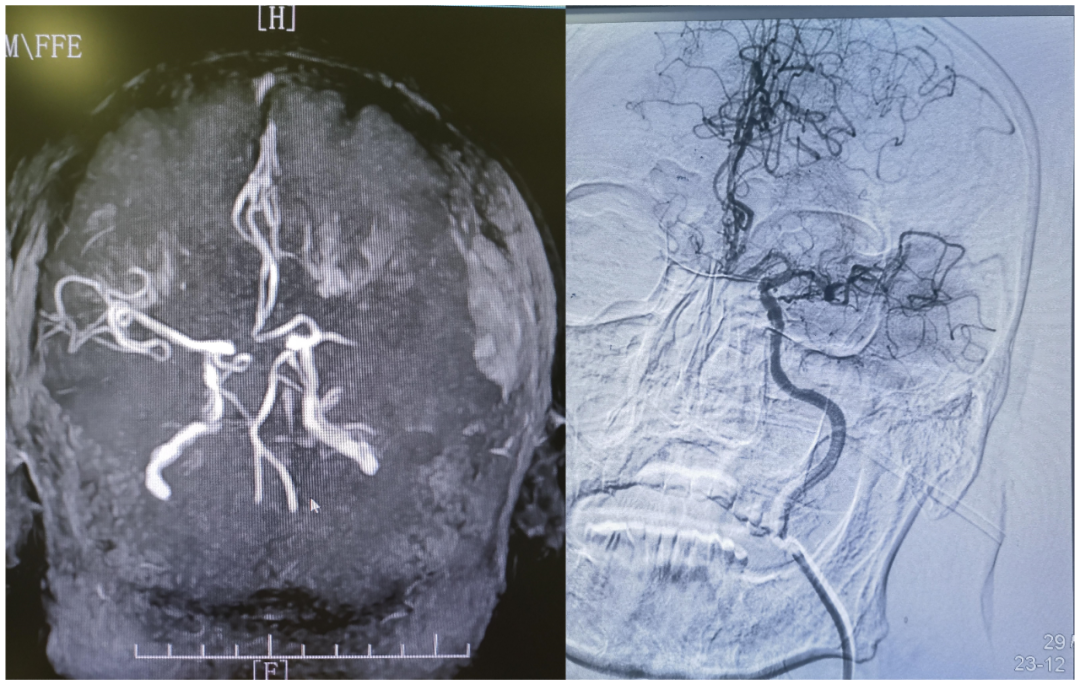

患者入院后,吴笃玮医师迅速为患者完成头颅CT等辅助检查,经专科查体,患者处于完全性混合性失语,口角向右歪斜,伸舌不配合,明确诊断为大脑动脉闭塞脑梗死、脑动脉闭塞、皮下血肿。结合患者临床症状及检查结果,溶栓为目前最佳治疗方案。

▲患者溶栓治疗前后头颅MRA对比

在患者符合溶栓条件的情况下,赵庆杰教授、刘素芳主任与神经内科团队立刻与患者家属详细沟通病情及溶栓方案,充分告知患者及患者家属溶栓的必要性、获益性及风险性,征得患者家属同意并签订知情同意书后,于23:50分给予患者阿替普酶溶栓治疗,治疗过程顺利。在进一步护理及治疗后,介入取栓治疗,取栓成功,大动脉成功开通,病情好转。